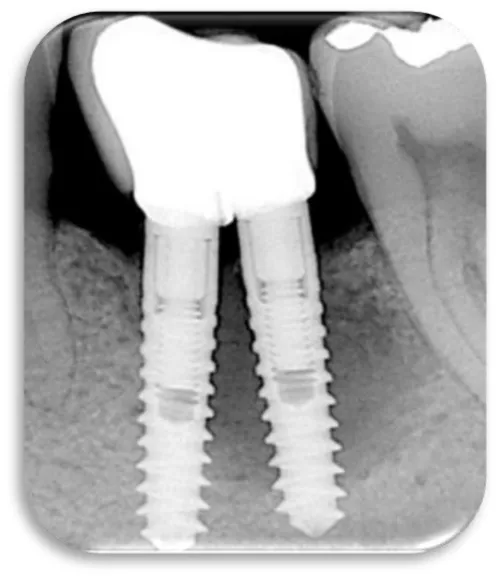

Two dental titanium implants were placed in a 37 years old, male patient. These two dental titanium implants were placed one year ago and their position is 36, they compensate the lower left first molar. The patient come to dental office on control because he felt pain in the area of dental implants. The pain, except during mastication, was also manifested during the brushing of the teeth, and was accompanied by bleeding from the gums. Gingiva was hyperemic and oedematous (Figure 36), and X-ray control images were also made, which can be seen below (Figure 37-40). During the process of probing, the dental probe drowned in bone pocket around the dental implants at a depth of 10 mm.